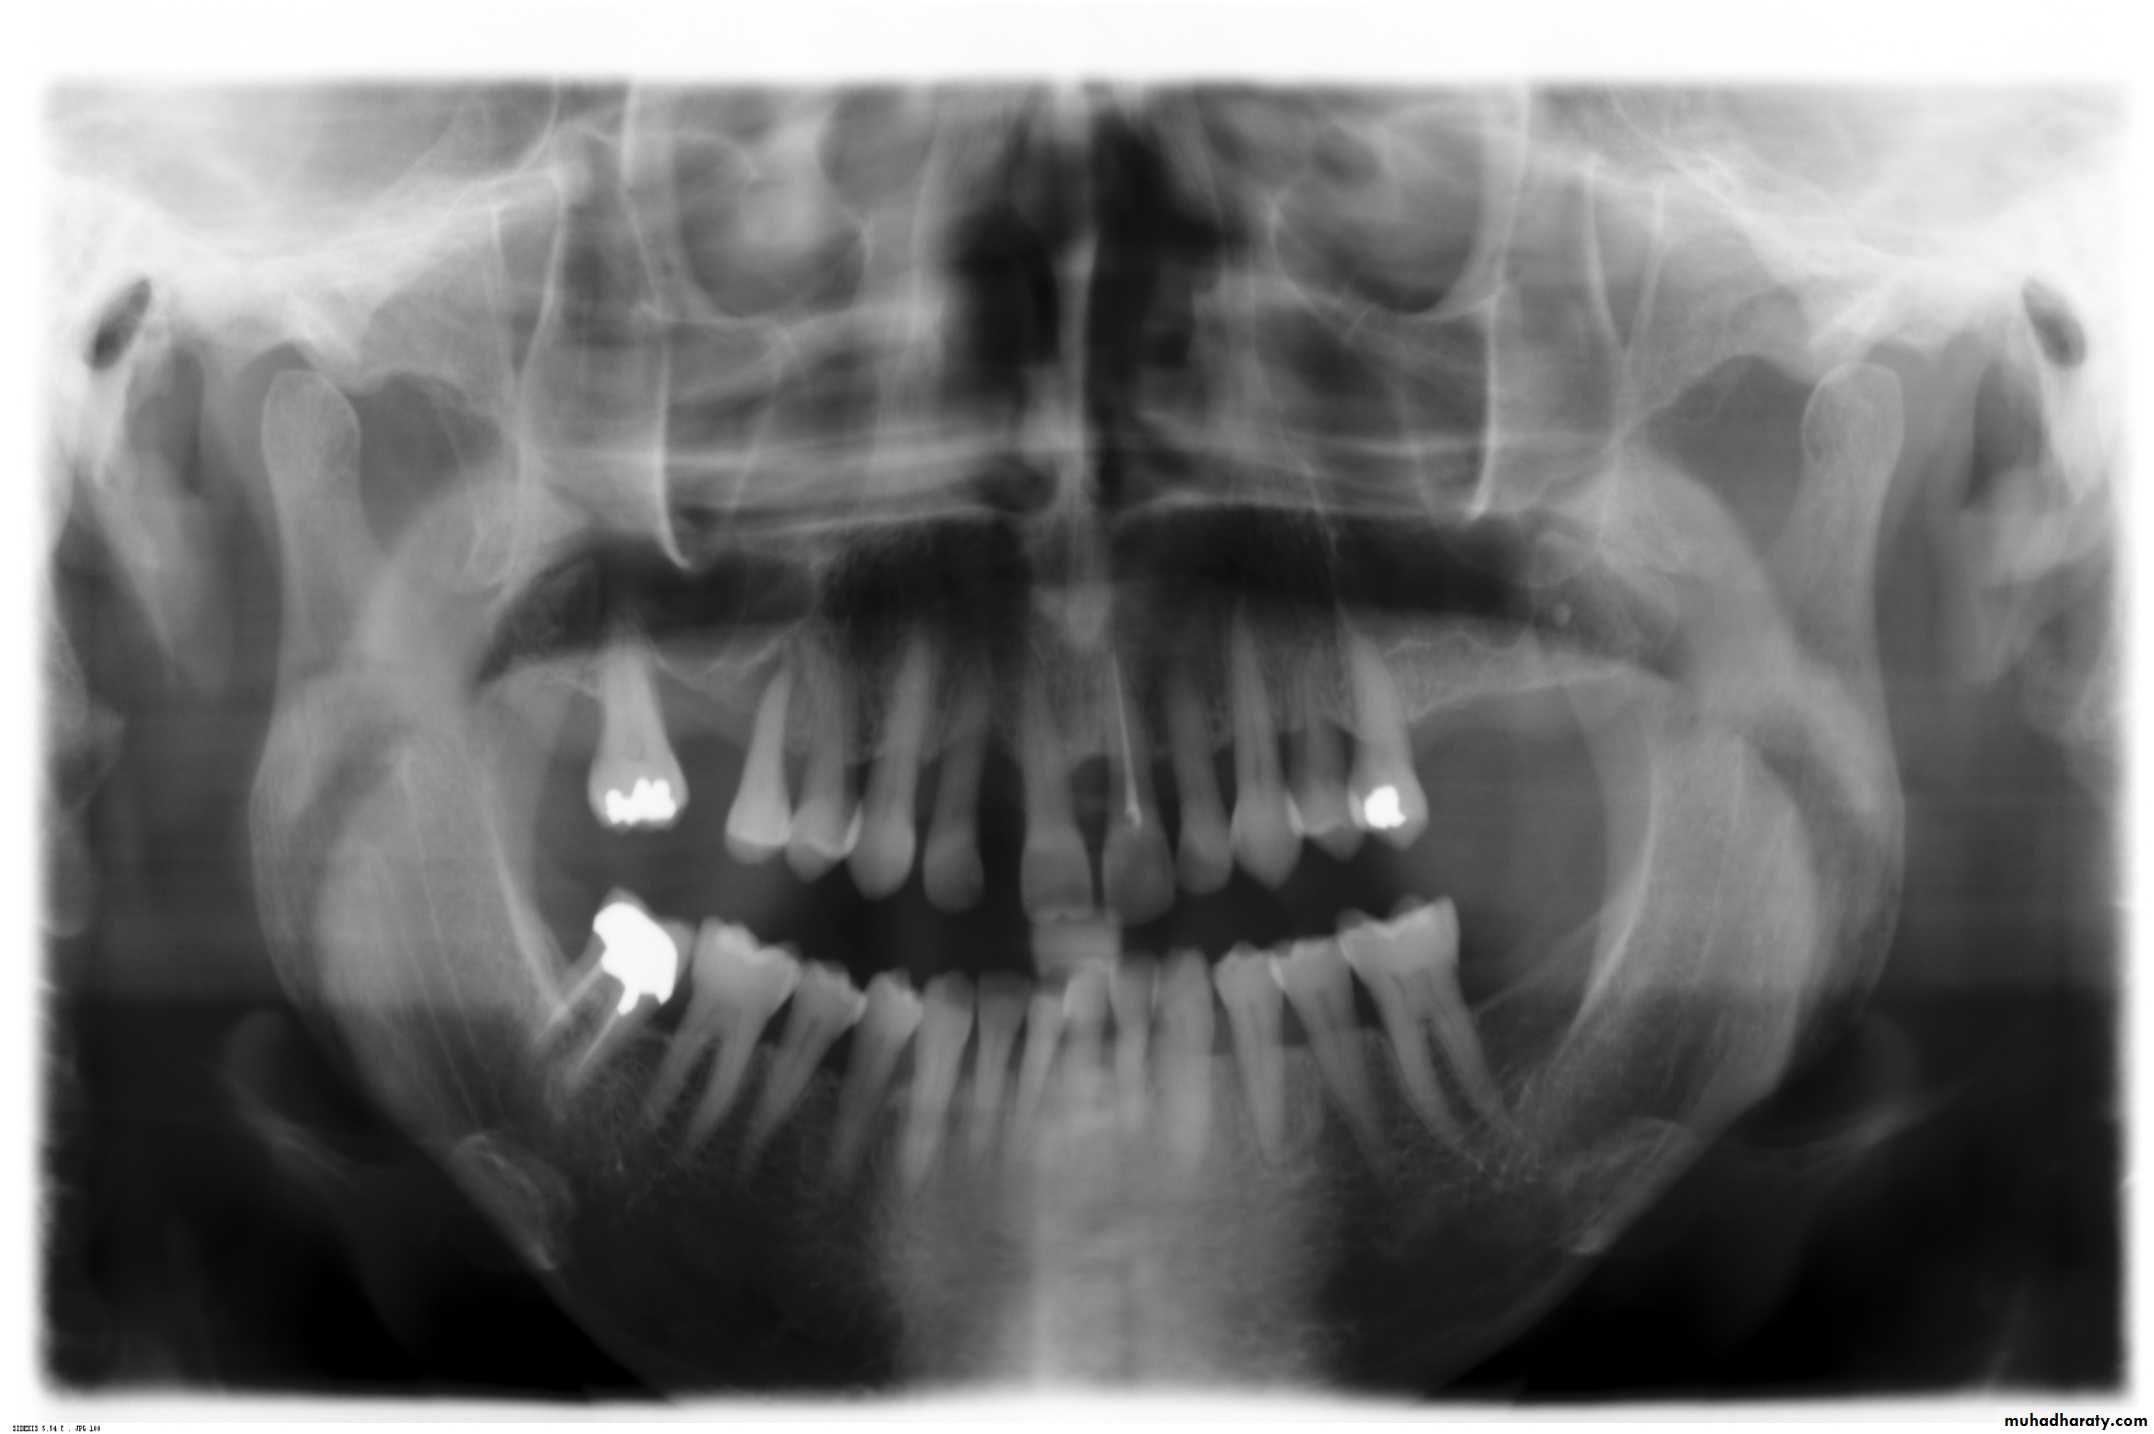

b. Radiographic examination

Panoramic radiograph, OPGPeriapical

Bitewing

9